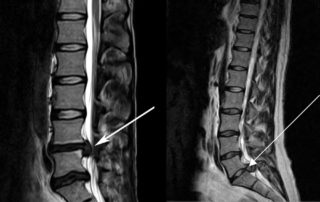

Злокачественные опухоли могут поражать как органы брюшной полости, так и костные структуры позвоночника. Чтобы точно определить локализацию новообразования пациентке назначают проведение магнитно-резонансной томографии. Данный метод диагностирования позволяет получить детализированную картину мягких и костных тканей.

Опухоли слева от позвоночника могут разрушать костную ткань и поражать соседние органы, поэтому при возникновении подозрений девушка должна немедленно обратиться за квалифицированной помощью.

МРТ показывает состояние мягких тканей, костей и хрящей

При подозрении на болезни сердца могут сделать ЭКГ, УЗИ сосудов. При патологиях позвоночника обязательно потребуется рентген. При разных нарушениях назначают МРТ, КТ, а также сдачу стандартных лабораторных анализов.